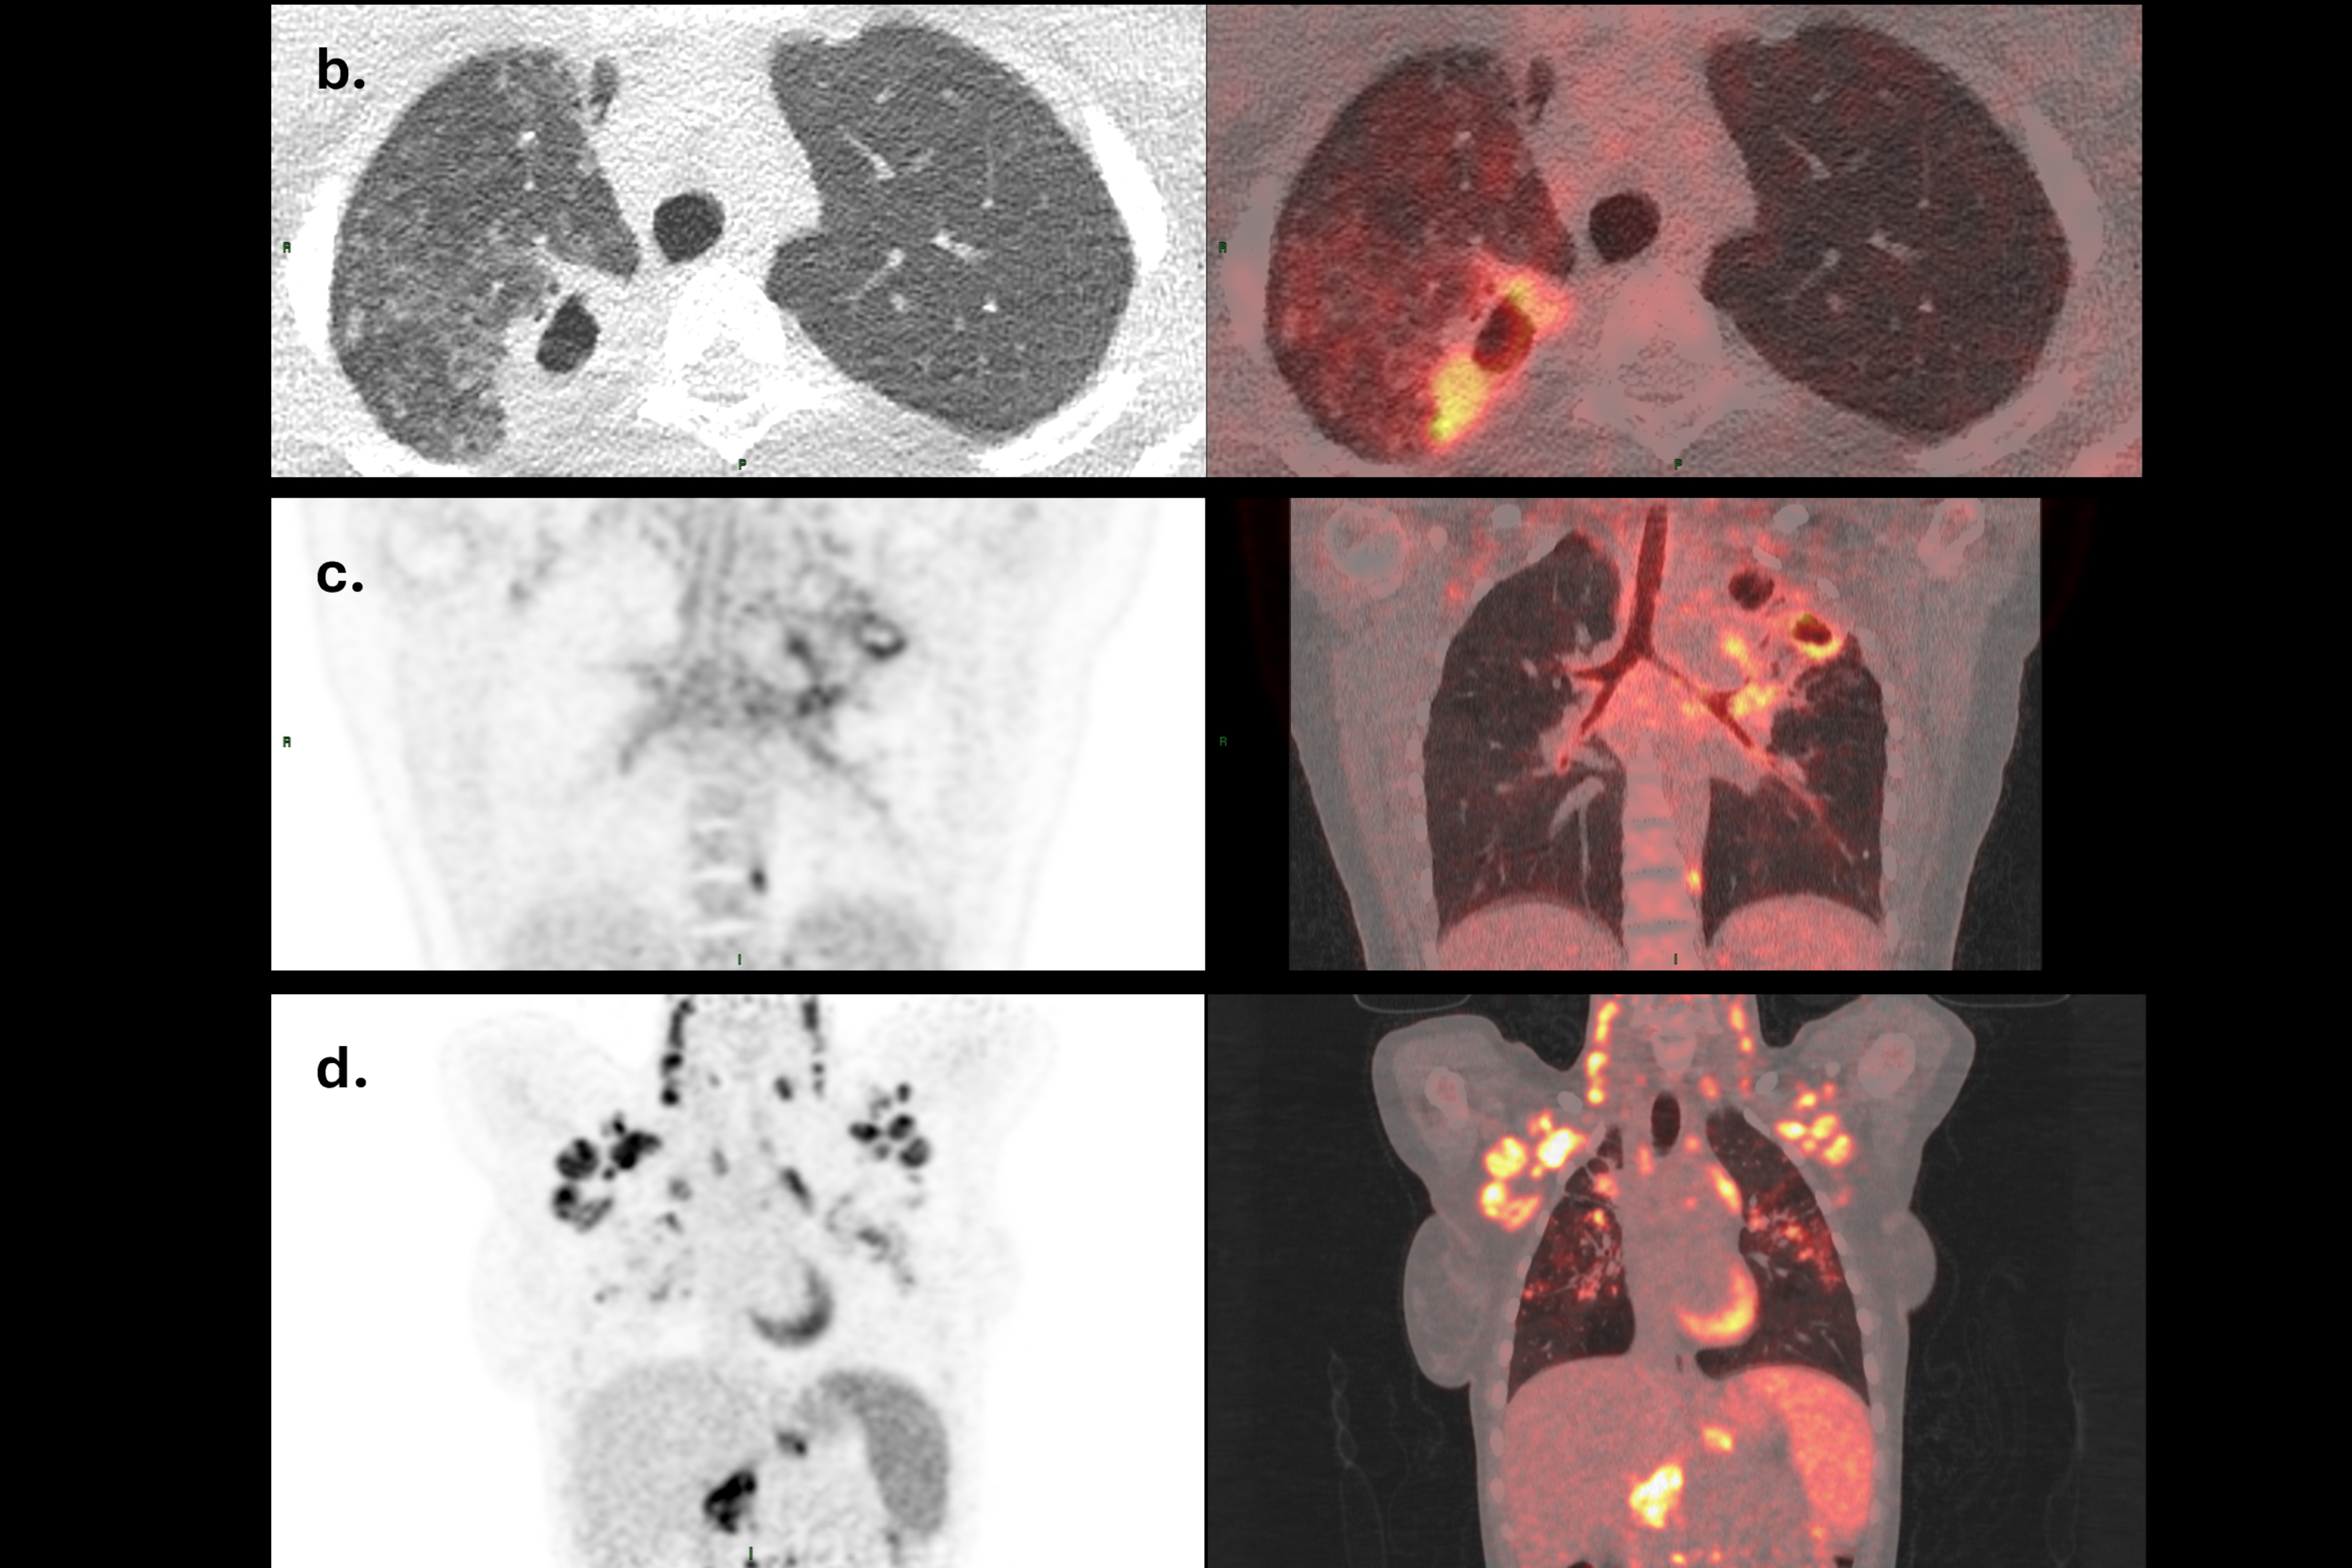

To explore the immunological changes that occur during adolescence, the DEFIANT study will analyse samples from 100 adolescents with pulmonary TB – a form of disease which primarily affects the lungs – alongside 200 healthy controls. Researchers will investigate how pubertal stage relates to inflammatory responses in the blood and sputum, and in turn how this drives disease severity. Severity will be assessed using PET/CT, a form of imaging that not only assesses the anatomy of the lungs but also gives important information about inflammation and metabolism.